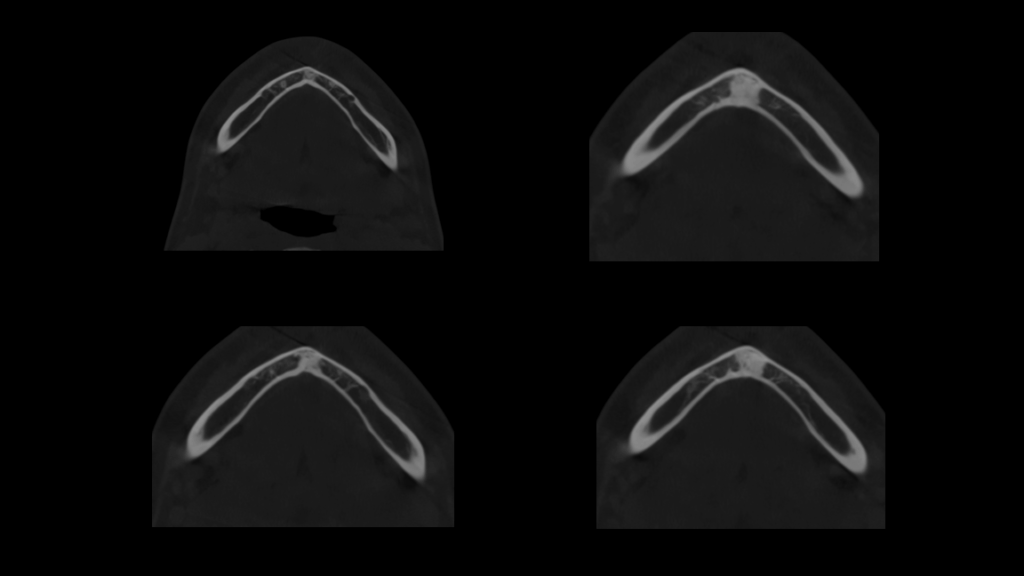

A la evaluación de la tomografía volumétrica (CBCT) en los cortes axiales (Figura 2) y transaxiales (Figura 3), se aprecia pieza supernumeraria en posición invertida localizada en zona anterior del maxilar superior, así mismo se observa disminución de la densidad a nivel coronario y reabsorción radicular externa a nivel del tercio cervical (ameloclasia).

CORTES AXIALES